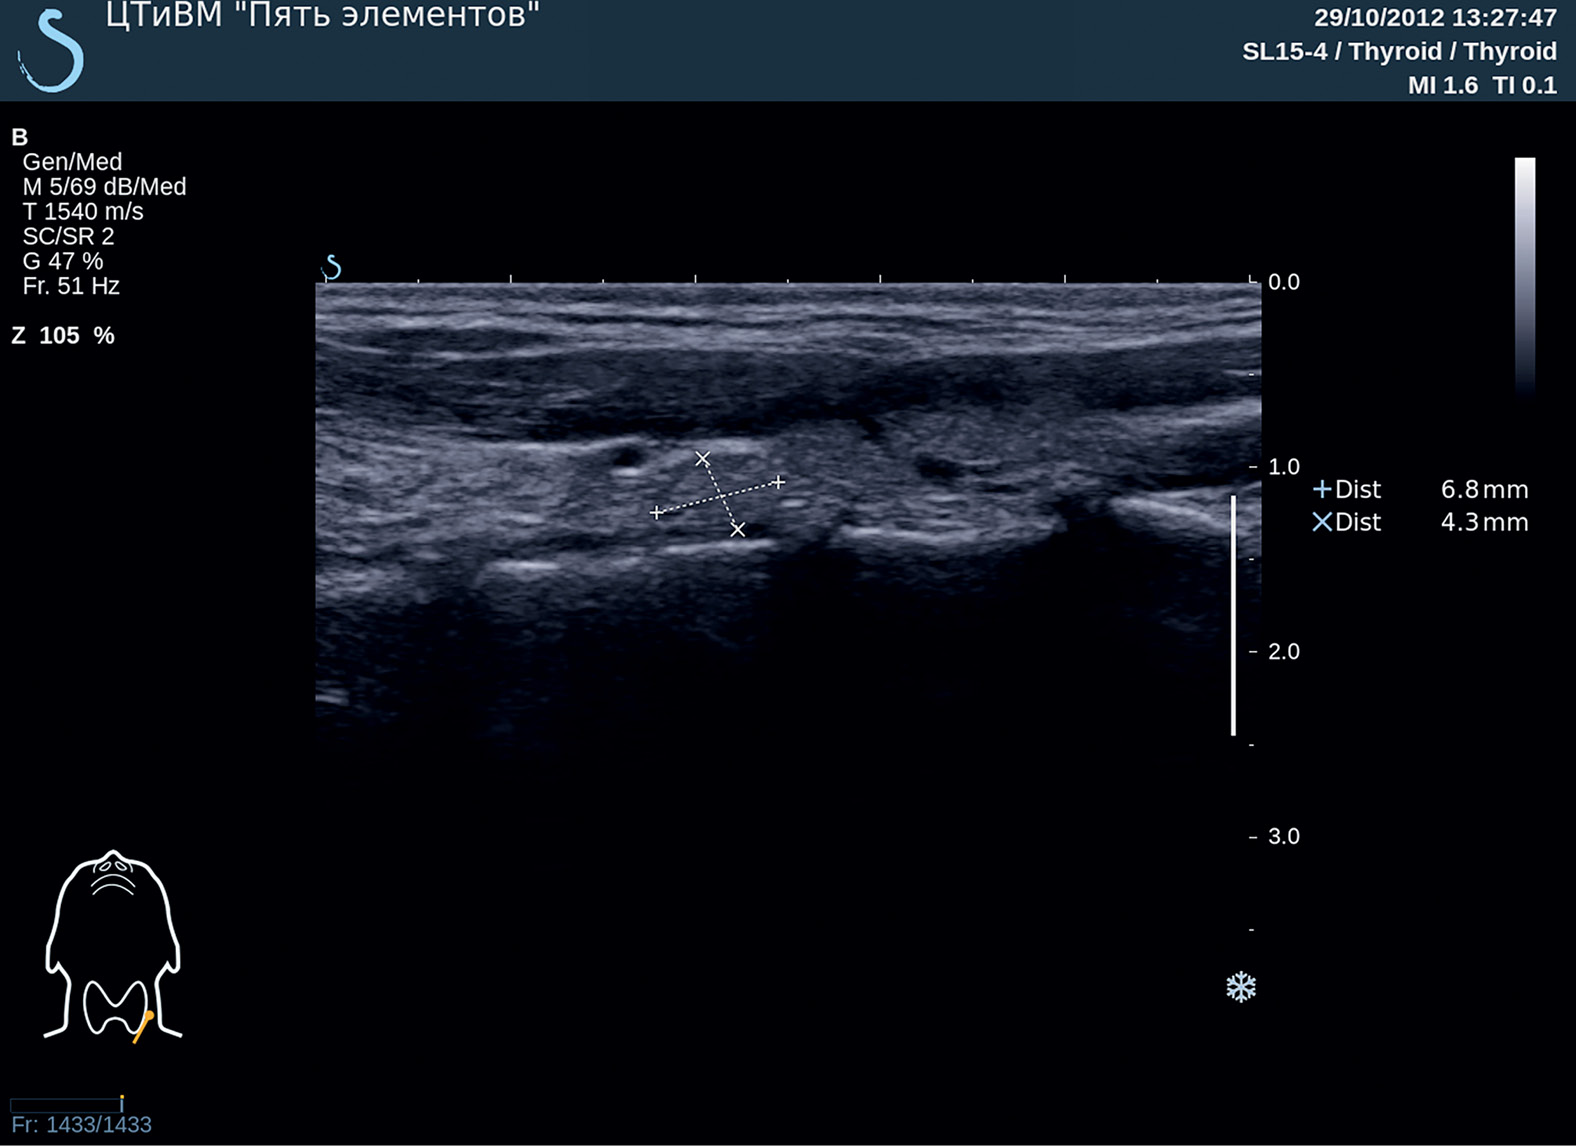

1. Рисунок 1. Ультразвуковое исследование околощитовидных желез пациентки М. Описание: Гиперплазия левой нижней околощитовидной железы. Эхографическая структура железы не изменена. | |